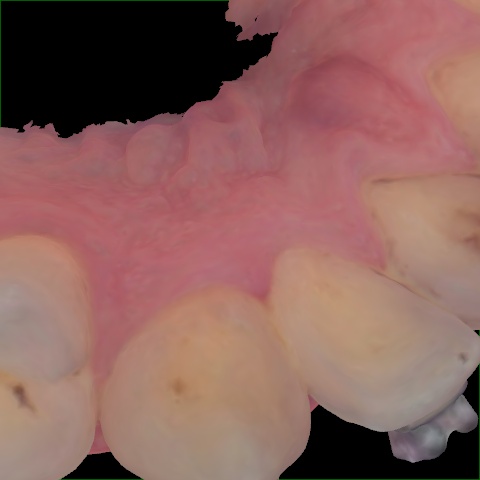

Image 1499 / 2000

NHD39969

Annotated as "Good"

Original Image Rendering Image